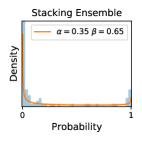

5.1 Distribution of Uncertainty Scores

Distribution of Uncertainty Scores Across Different Severity Levels As explained in Section 3, each uncertainty metric essentially defines an order/ranking among the data points. We conducted an analysis to better understand what data will be assigned high uncertainty under a particular uncertainty metric . Picking out the highest ranked data points (), we calculated the ratio of data points from each SL. Figure 4 summarizes the results as box plots for the Kaggle-DR and the Messidor-2 datasets; additional detailed statistics can be found in Table S.1 in the supplementary materials. From the plot and table, SL1 & SL2 examples account for a higher proportion among the top-ranked uncertain examples across the three ensemble methods. This finding matches our intuition that incipient disease examples (SL1 & SL2) are more likely to be considered uncertain by ensemble methods due to their ambiguity.

Comparing the three ensemble methods in Figure 4, the stacking ensemble method has the highest ratios of SL1 & SL2 data among the high-uncertainty examples it identified under both mean and var. TTA showed slightly better performance than MC-dropout but still falls behind the stacking ensemble method. Considering the fact that SL0 examples accounted for the majority of the dataset, the stacking ensemble method was much more precise (specific) in selecting truly ambiguous data points that were difficult to classify. From Figure 3, we can also see that the stacking ensemble method greatly outperformed the other two methods in finding false negatives under both mean and var uncertainty metrics.

In contrast, the MC-dropout method showed the worst overall performance among the three, as it can be seen from the high ratios of SL0 examples among the uncertain negatives in Figure 4. The histograms in Figure 2 provides another perspective to look into the phenomenon, where a decent proportion of MC-dropout model’s predictions on SL0 inputs entailed low confidence (far from 0 or 1), which from another angle explained why MC-dropout was less specific in terms of lower FNP; many no-DR inputs (i.e. SL0) were erroneously assigned high uncertainty by MC-dropout models.

It is still an open question why the evaluated MC-dropout networks signaled relatively high uncertainty on SL0 & SL3 & SL4 data that are less likely to be ambiguous. We conjecture that much of the “uncertainty” indicated by disagreement among test-time dropout samples actually reflects the stochastic nature of dropout networks rather than the real decision uncertainty associated with the data. It is worth noting that the MC-dropout model we evaluated was not weak per se; they all achieved above Area Under Curve (AUC) scores on test sets. The weakness of individual test-time samples (which explains their low-confidence predictions on SL0 & SL3 & SL4) might have been hidden when they are aggregated into an ensemble—a well-known advantage of ensemble learning. Our results suggested that the uncertainty information given by implicit ensemble methods such as MC-dropout and TTA might not be as reliable as that from explicit ensemble approaches (e.g., stacking ensembles). Similar findings on MC-dropout can be found in some previous papers [1].